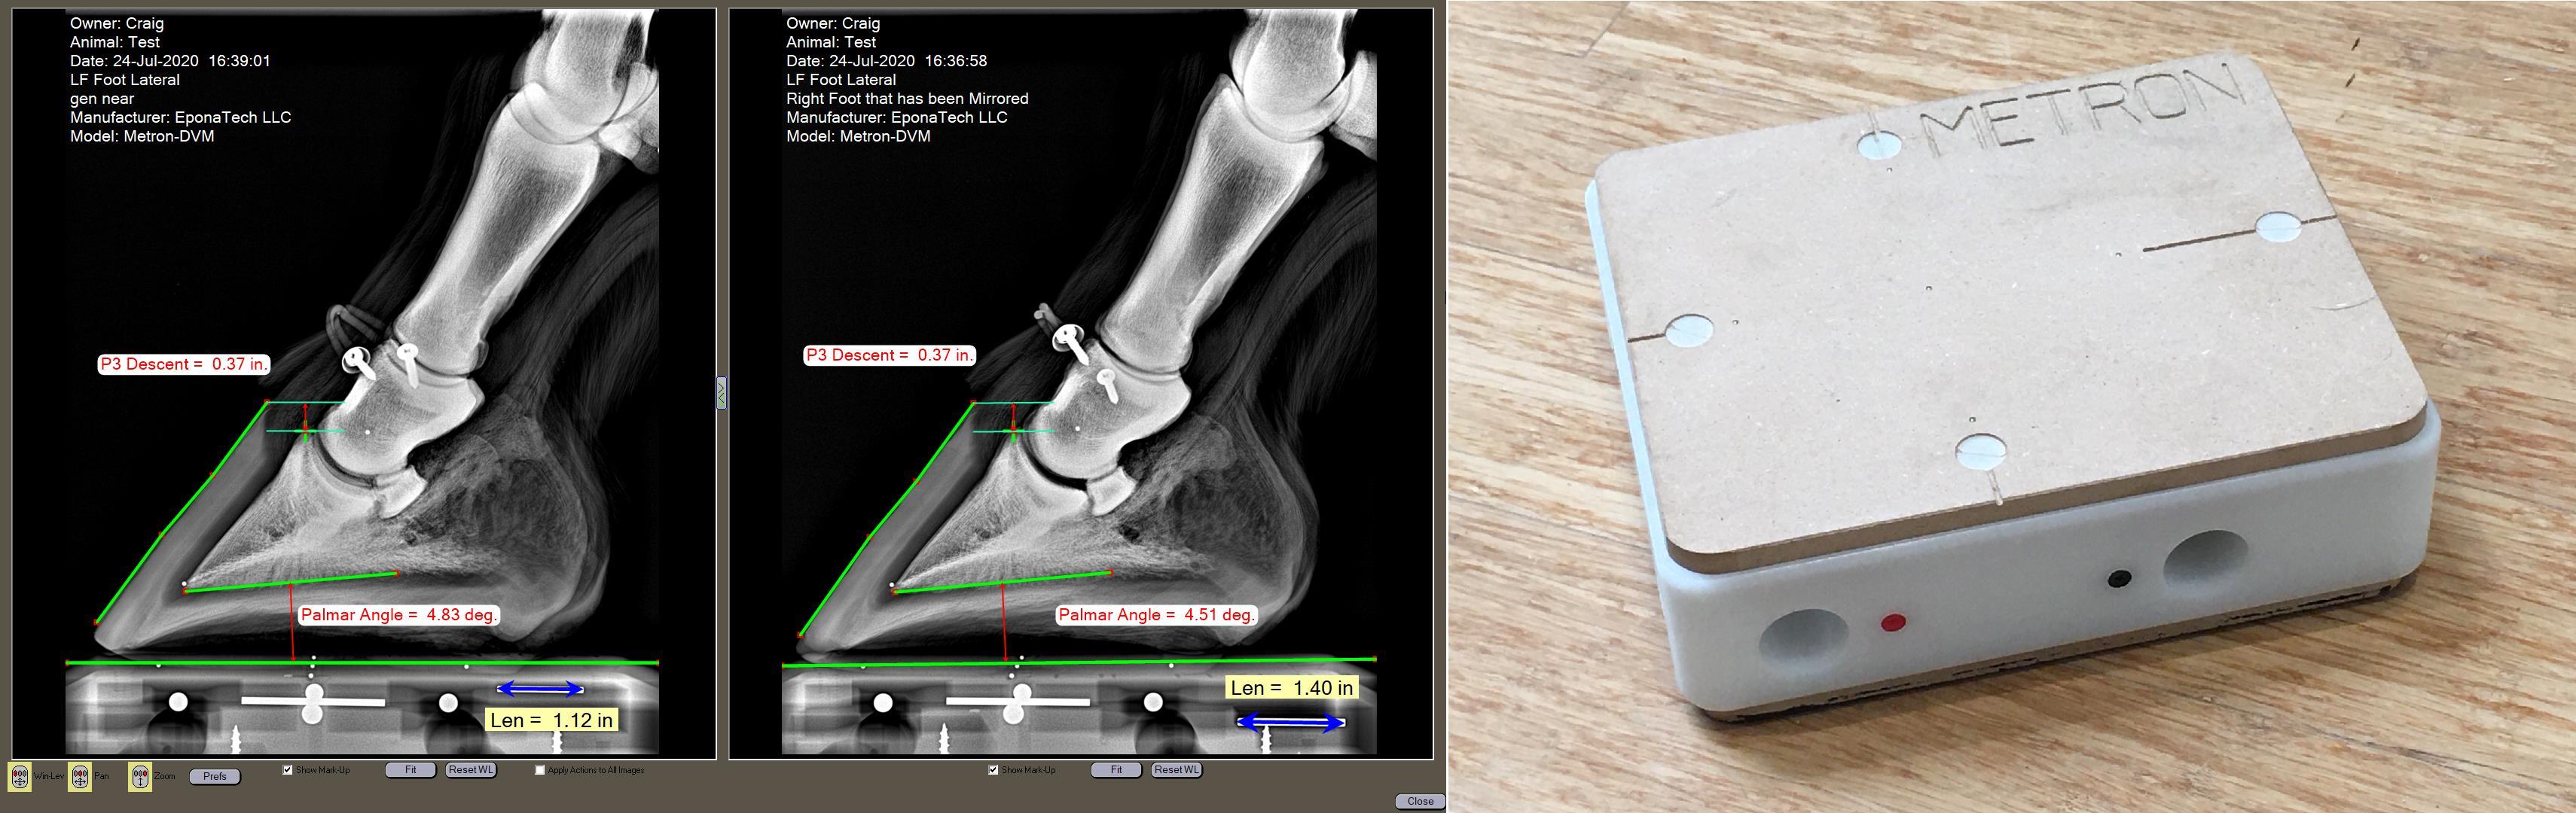

Innovative Metron Block

Explore the innovative 'Metron Block' for accurate hoof measurements

Utilize Metron software for easy and precise measurements

Join Dr. John Craig, PhD in this exclusive course to master the art of equine hoof imaging. Learn the techniques to capture accurate images and make measurements, in particular, using the revolutionary 'Metron Block'. Enhance your skills and achieve precision in equine hoof analysis. Even practicing equine veterinarians will learn something new in this webinar! Enroll now to elevate your imaging capabilities!